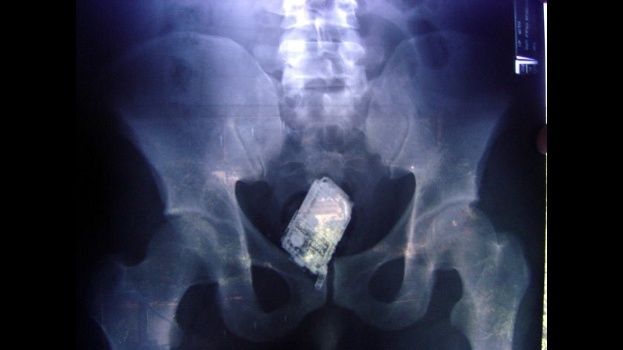

Al tercer preso, al pasar por los rayos X, se le descubrieron diez minicelulares con auriculares en su estómago y fue sometido a una operación para retirarle todos los aparatos.